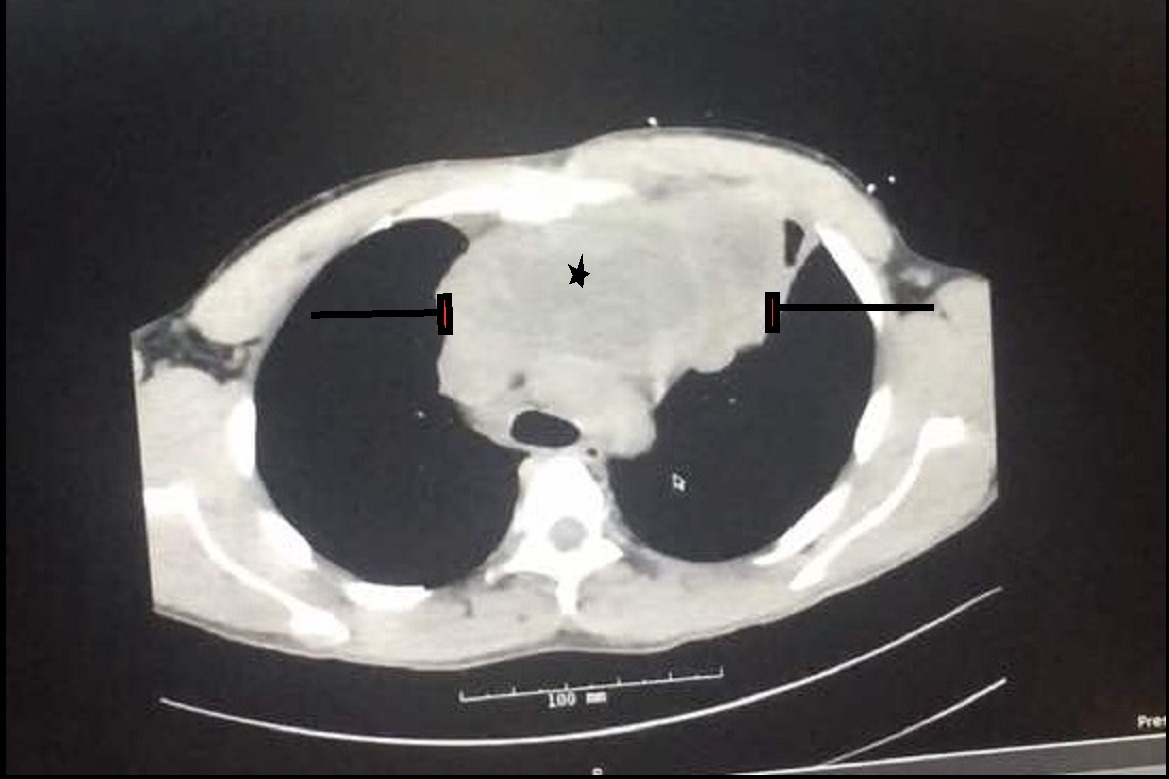

During this past month, Rowie was experiencing facial congestion, chest pain, and jugular venous distention. Though he knew this was problematic, the fear of facing outrageous bills and being without insurance in a foreign country led him to wait until the pain was no longer bearable. Having severe difficulty breathing, he was taken to the Emergency Room at Rush Medical Center in Chicago, IL where a chest CT revealed a 9x10x13cm mass in the anterior mediastinum, a mass bigger than his own heart, pressuring his trachea and major blood vessels.

A team of specialists including Cardiothoracic surgeons, Interventional Radiologist and Pulmonary & Critical care were immediately informed about the case and planned an emergency biopsy guided through CT. Sadly, it revealed what all doctors expected: Primary Mediastinal B-Cell Lymphoma - one of the most aggressive and fast-growing Lymphomas. Following his diagnosis with no insurance of any kind, not even basic coverage, Rowie was discharged and his hope for a cure was far from possible.